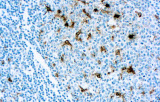

- Assegnazione del lignaggio & principali diagnosi differenziali: Fenotipizzazione cellule B vs cellule T (es. CD20 vs CD3), supportata da fattori di trascrizione nucleari delle cellule B come PAX5 quando i marcatori pan-B sono deboli/assenti.

- LLC/LLS: co-espressione caratteristica di CD5 e CD23 nelle cellule B CD20+ (l'interpretazione richiede consapevolezza del pattern perché sono presenti cellule T reattive).